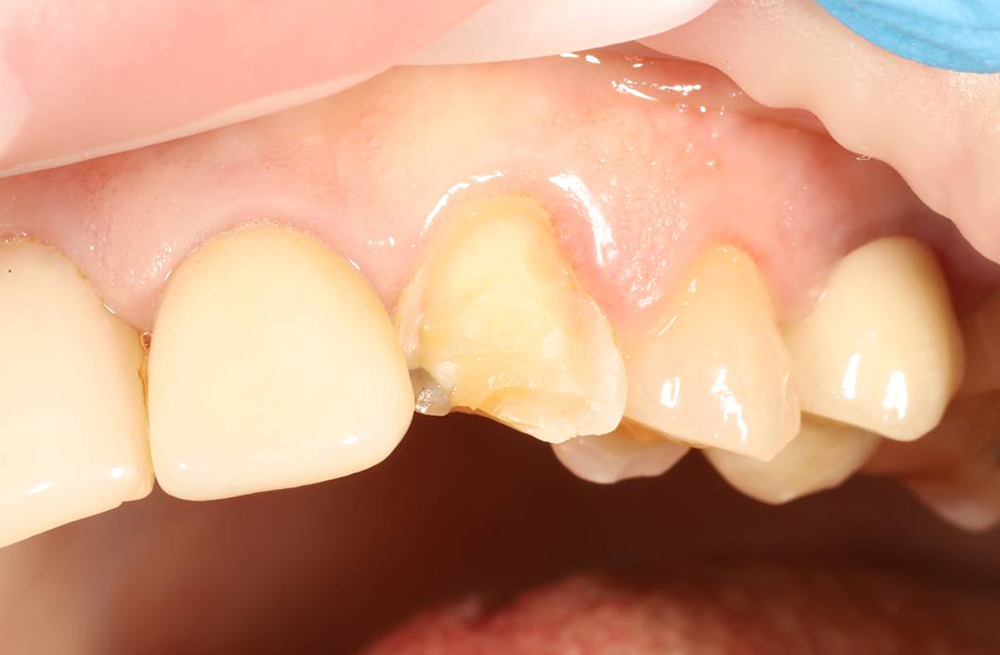

Восстановление зуба при кариесе на внешней стороне зуба у десны

Эстетическая реставрация переднего зуба для устранения видимого дефекта